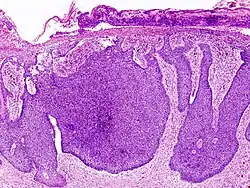

![]() |

Lepromatous leprosy | Skin biopsy showing epidermal atrophy and multiple dermal infiltrates. | Category: Histopathology of leprosy | Leprosy |